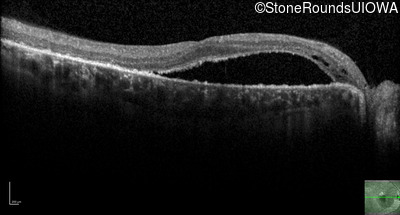

Optical Coherence Tomography - Left - 20/20 -2

Exemplar / OCT Stack